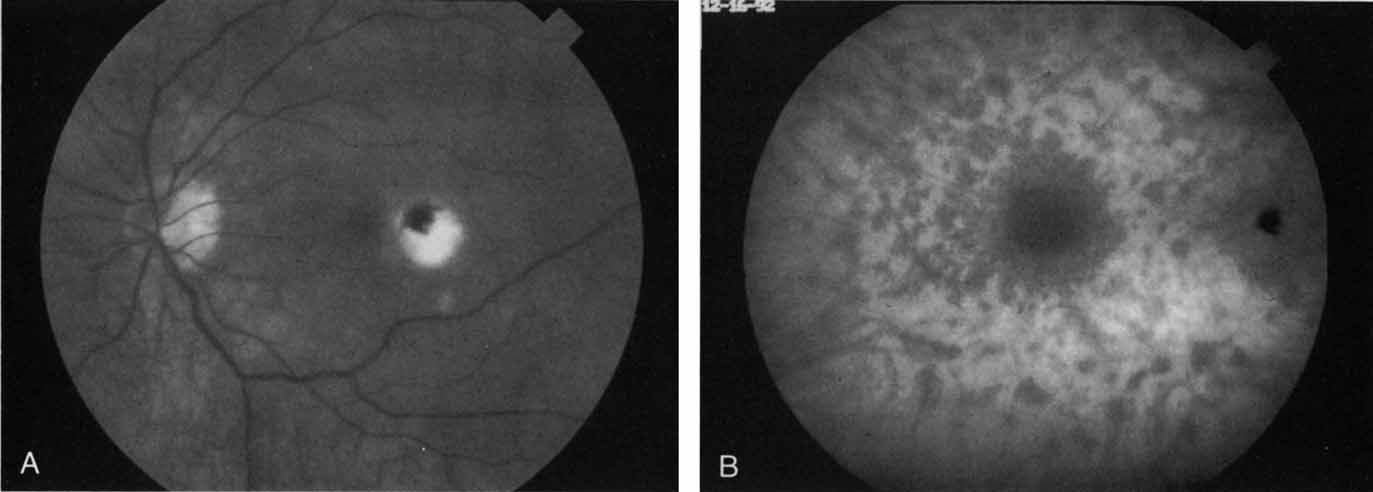

More recently, ICG angiography has begun to play an important role in the management of patients with occult CNV. In particular, the identification and management of two subsets of occult CNV, namely retinal angiomatous proliferation (RAP)34 and polypoidal choroidal neovascularization (PCV),35 are greatly enhanced with ICG angiography. RAP is a distinct subgroup of neovascular AMD in which angiomatous proliferation within the retina is the first manifestation of the process of neovascularization. As the neovascularization proliferates into the outer retina and subretinal space, the angiomatous proliferation is then surrounded by dilated retinal vessels, hemorrhages (preretinal, intraretinal, and subretinal), and exudates. One or more of the related, compensatory retinal vessels perfuse and drain the neovascularization, occasionally forming a retinal–retinal anastomosis (RRA). In these patients, the same indistinct staining seen in occult CNV is present on a fluorescein angiogram. Therefore, most cases of RAP require the use of ICG angiography to make the diagnosis (Fig. 11).34

ICG angiograms of RAP lesions reveal a focal area of intense hyperfluorescence corresponding to a so-called hot-spot of neovascularization with some late extension of the leakage within the retina caused by intraretinal neovascularization (IRN) within the deep layers of the retina. As the IRN progresses down into the subretinal space, the neovascularization present in the choroid joins the IRN to form a large, neovascular complex. At this stage, clinical and angiographic evidence of a vascularized PED (V-PED) is often present. ICG is the preferred method of imaging a V-PED because the serous component of the PED remains hypofluorescent while the vascular component displays hyperfluorescence. ICG angiography may be able to capture direct communication between the retinal and choroidal component of the neovascular complex as they meet to form a retinal choroidal anastomosis (RCA).34 Treatment options of RAP lesions include: traditional laser photocoagulation of the stage 1 and early stage 2 lesions, surgical excision of stage 2 lesions in conjunction with laser diathermy, as well as PDT, alone and in combination with other treatments, particularly triamcinolone acetonide.36,37 Other therapies, both singly and in combination, are currently undergoing investigation for this unique form of neovascular AMD.